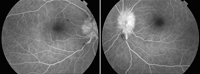

Figura 1). La tomografía de coherencia óptica (OCT) macular de OD muestra desprendimiento seroso subfoveolar, siendo la OCT del OI normal (

Figura 2. OCT macular OD y OI respectivamente. Se observa en OCT macular derecho desprendimiento neurosensorial. OCT izquierdo normal.

Figura 4), normalizándose la OCT macular (

Figura 5. OCT macular dos meses después del diagnóstico con normalización bilateral.